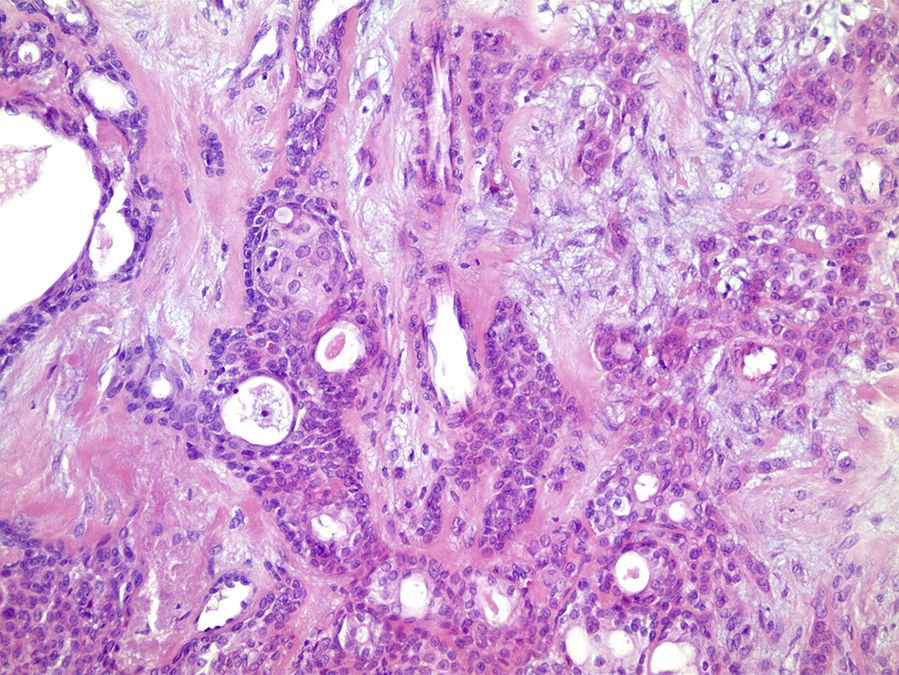

O exame histopatológico apresenta neoplasia geralmente bem delimitada por cápsula de tecido conjuntivo fibroso, com parênquima constituído por células epiteliais ductais e células mioepiteliais. Essas células frequentemente exibem diferentes morfologias gerando arquiteturas teciduais distintas dentro do mesmo tumor, motivo pelo qual foi denominado pleomórfico2,3. Podem ser encontradas áreas ductiformes, sólidas, mixoides, hialinas, plasmocitoides, osteoides e condroides, além de metaplasia escamosa6,7.

Os cortes histológicos, corados em hematoxilina e eosina, mostraram neoplasia de glândula salivar benigna, constituída por células epiteliais e mioepiteliais, parcialmente envolvida por fina cápsula de tecido conjuntivo fibroso (fig. 5). As células epiteliais encontravam‐se formando lençóis ou estruturas ductiformes, enquanto as células mioepiteliais formavam áreas mixoides, hialinas (fig. 6) ou exibiam aspecto plasmocitoide (fig. 7). O diagnóstico de adenoma pleomórfico foi confirmado. Paciente queixou‐se de desconforto no palato quando se alimentava, durante as 2 primeiras semanas após cirurgia. O paciente está sendo acompanhado clinicamente e, 2 anos após a cirurgia, não apresenta sinais de recidiva da lesão (fig. 8).

Os cortes histológicos mostraram neoplasia benigna de glândula salivar, envolvida por cápsula de tecido conjuntivo fibroso (fig. 14). O parênquima neoplásico é constituído por células epiteliais dispostas em lençóis e estruturas ductiformes, além de células mioepiteliais formando áreas mixoides e hialinas (fig. 15) ou apresentando‐se com morfologia plasmocitoide (fig. 16). O diagnóstico de adenoma pleomórfico foi confirmado. A paciente relatou ausência de dor no pós‐operatório e manteve utilização da placa de acrílico por 4 semanas. A paciente encontra‐se em acompanhamento e o exame clínico após 2 anos da remoção cirúrgica mostrou adequada cicatrização e ausência de sinais de recidiva da lesão (fig. 17).